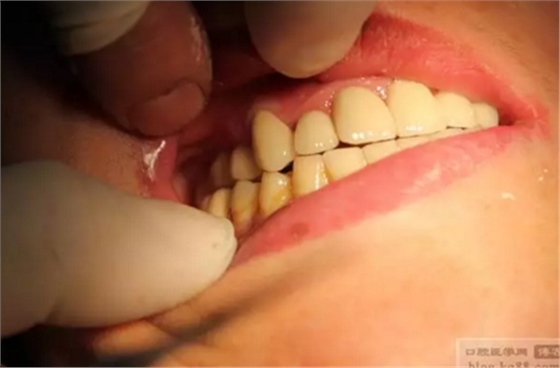

雙側(cè)種植牙分別做成連冠、前牙做成單冠,左下6、7連冠,(戴牙后照片)